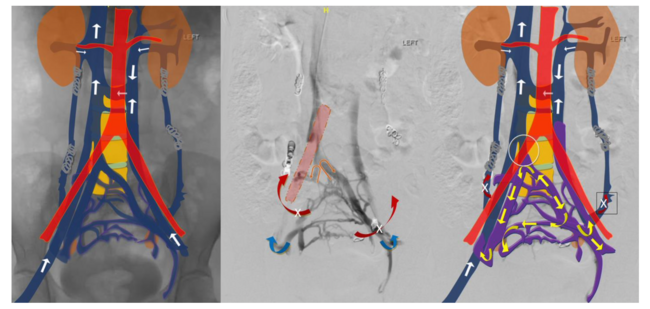

The patient’s previous contrast-enhanced computed tomography (CECT) scan was reviewed (Figure 1), showing duplication of the inferior vena cava (IVC). The left common iliac vein was continuing as the left IVC, which was communicating with the right IVC through retroperitoneal collaterals in the lumbar region. The left internal iliac vein (IIV) was joining the right IIV. The right IIV (a common trunk for both IIVs) was extrinsically compressed by the right common iliac artery (Figure 2). Both gonadal veins were dilated. Magnetic resonance imaging of the pelvis showed persistent flow voids in the parametrium and adnexa, consistent with pelvic venous congestion (Figure 1).

Endovascular treatment was planned. Under aseptic precautions, the right internal jugular vein was accessed and a 5F sheath was placed. Using a 0.035" guidewire and 5F multipurpose catheter, the left IIV was cannulated. The venogram (Figure 3) showed significant extrinsic compression stenosis in the junction of the common venous trunk, correlating with the CECT (Figure 2). Multiple venous collaterals were seen in the pelvis with stagnation of the contrast.

On-table intravascular ultrasound (IVUS) confirmed the findings (Figure 2). The diameter of the venous trunk was 13.4 mm caudal to the narrowing. There was a pressure gradient of 5 mm Hg across the narrowing. A 16 mm x 6 cm Wallstent endoprosthesis self-expanding stent (Boston Scientific) was deployed across the narrowed portion of the common venous trunk (Figure 4). The stent was opened with a 14 mm x 4 cm balloon. Check venogram showed a brisk antegrade flow. The pressure gradient had reduced to 2 mm Hg. The patient had an uneventful recovery and was asymptomatic on follow-up at 6 months.